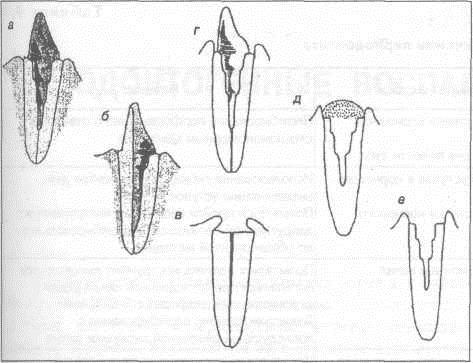

Культя зуба это

Культя зуба это 106 фото